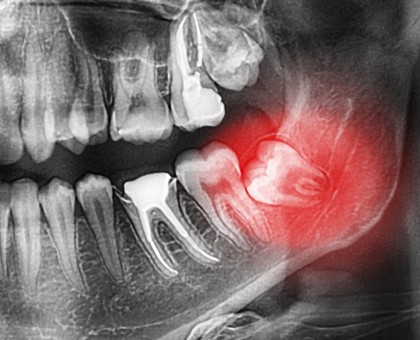

La radiographie est indispensable dans le domaine de la médecine dentaire. Elle permet d'examiner avec précision la structure dentaire et de poser des diagnostics justes. Elle est aussi utile si une intervention chirurgicale est envisagée. Lire la suite